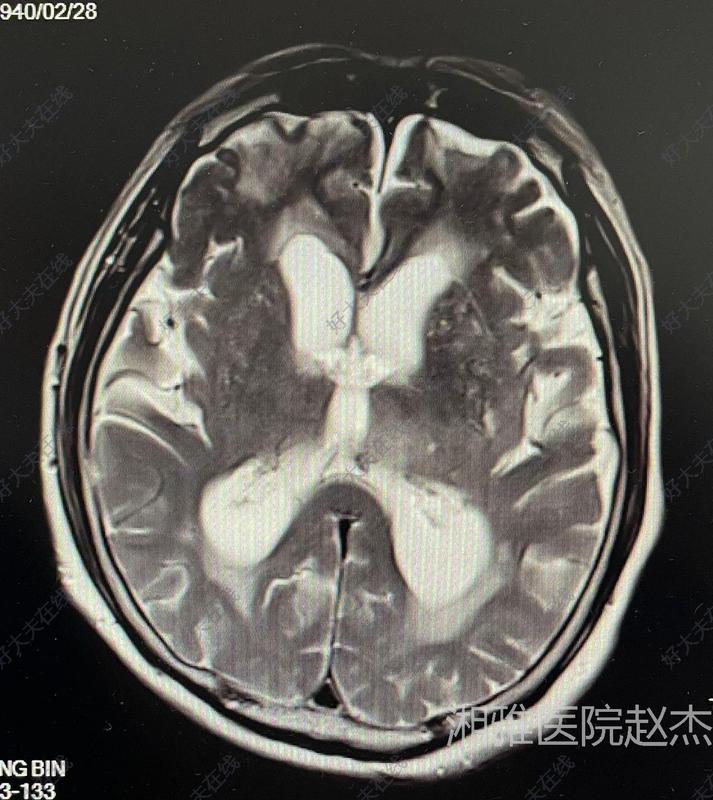

患者女性,18歲,4年前因頭痛行磁共振檢查發(fā)現(xiàn)腦積水,于2019年8月1日在我院行第三腦室底造瘺術(shù)(詳見(jiàn)2020-8月科普文章),手術(shù)順利,術(shù)后定期隨訪。因?yàn)橐咔樵蚪?年未來(lái)我院復(fù)查,昨日來(lái)院復(fù)查,恢復(fù)良好,沒(méi)有神經(jīng)功能損害,學(xué)業(yè)順利,作為主管醫(yī)生感到非常有成就感。當(dāng)時(shí)頭顱磁共振(2019-7)提示:梗阻性腦積水。昨天復(fù)查頭顱磁共振平掃(2023-7)提示腦積水緩解,未見(jiàn)復(fù)發(fā)。總結(jié):對(duì)于梗阻性腦積水,尤其女性患者,首選第三腦室底造瘺術(shù),可以避免長(zhǎng)期的分流管依賴(lài),防止將來(lái)懷孕時(shí)分流管堵塞;腦室腹腔分流手術(shù)相對(duì)比較簡(jiǎn)單,但是也有很多的并發(fā)癥。豐富經(jīng)驗(yàn)的神外團(tuán)隊(duì)能夠根據(jù)患者的情況采取個(gè)體化的治療方案,為病友帶來(lái)福音。

老年患者腦積水